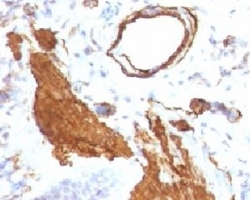

- Genetic validation

- Main image

- Experimental details

- Formalin-fixed, paraffin-embedded human Leiomyosarcoma stained with alpha Smooth Muscle Actin antibody (ACTA2/791). This image was taken for the unmodified form of this product. Other forms have not been tested.